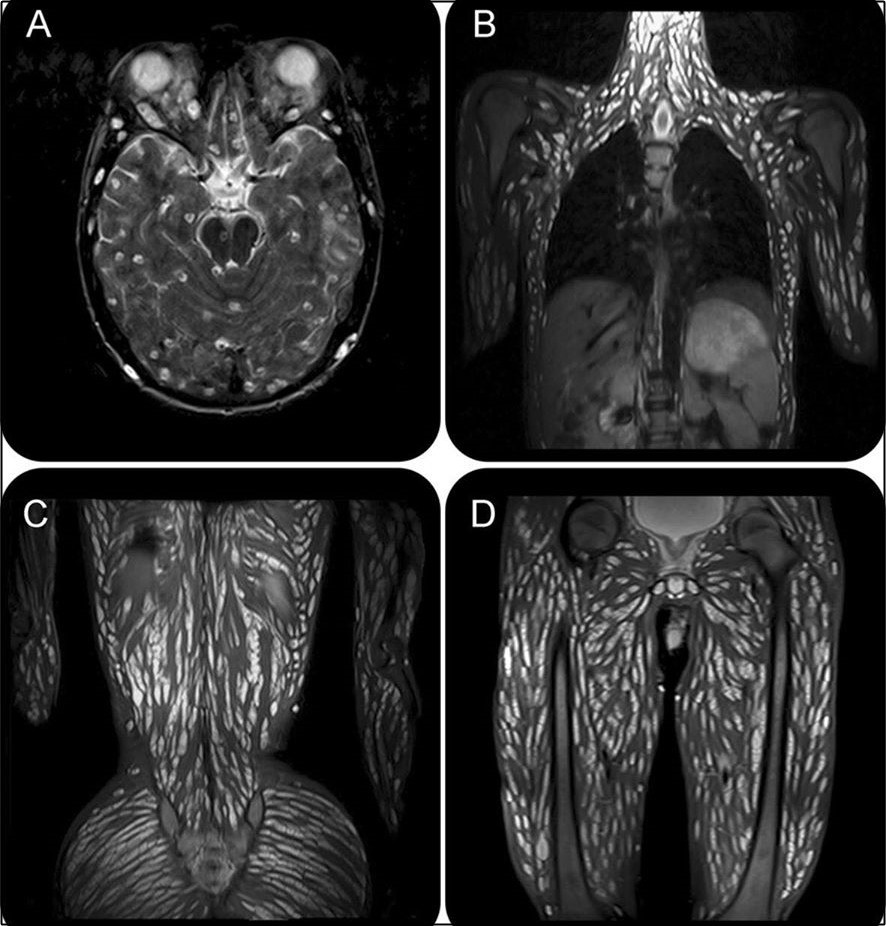

Sau những chẩn đoán ban đầu, bác sĩ cho tiến hành chụp cộng hưởng từ MRI và phát hiện ra mô não, đầu, ngực, bụng và chân tay của bệnh nhân phủ đầy sán dây, trông cực kỳ khủng khiếp. Bệnh nhân được xác nhận là nhiễm cysticercosis (bệnh nhiễm ấu trùng sán dây lợn).

Qua tìm hiểu, bác sĩ biết được rằng bệnh nhân đã ăn thịt heo chín tái hoặc chưa chín kỹ cùng với rau, trứng, trái cây. Và rất có thể tay của bệnh nhân không sạch sẽ nên mới dẫn tới tình trạng sán dây phủ kín cơ thể như vậy.

May mắn thay, bệnh nhân được điều trị bằng một loạt thuốc chống giun, steroid và thuốc chống động kinh. Sau đó, tình hình của chàng trai này đã cải thiện đáng kể.